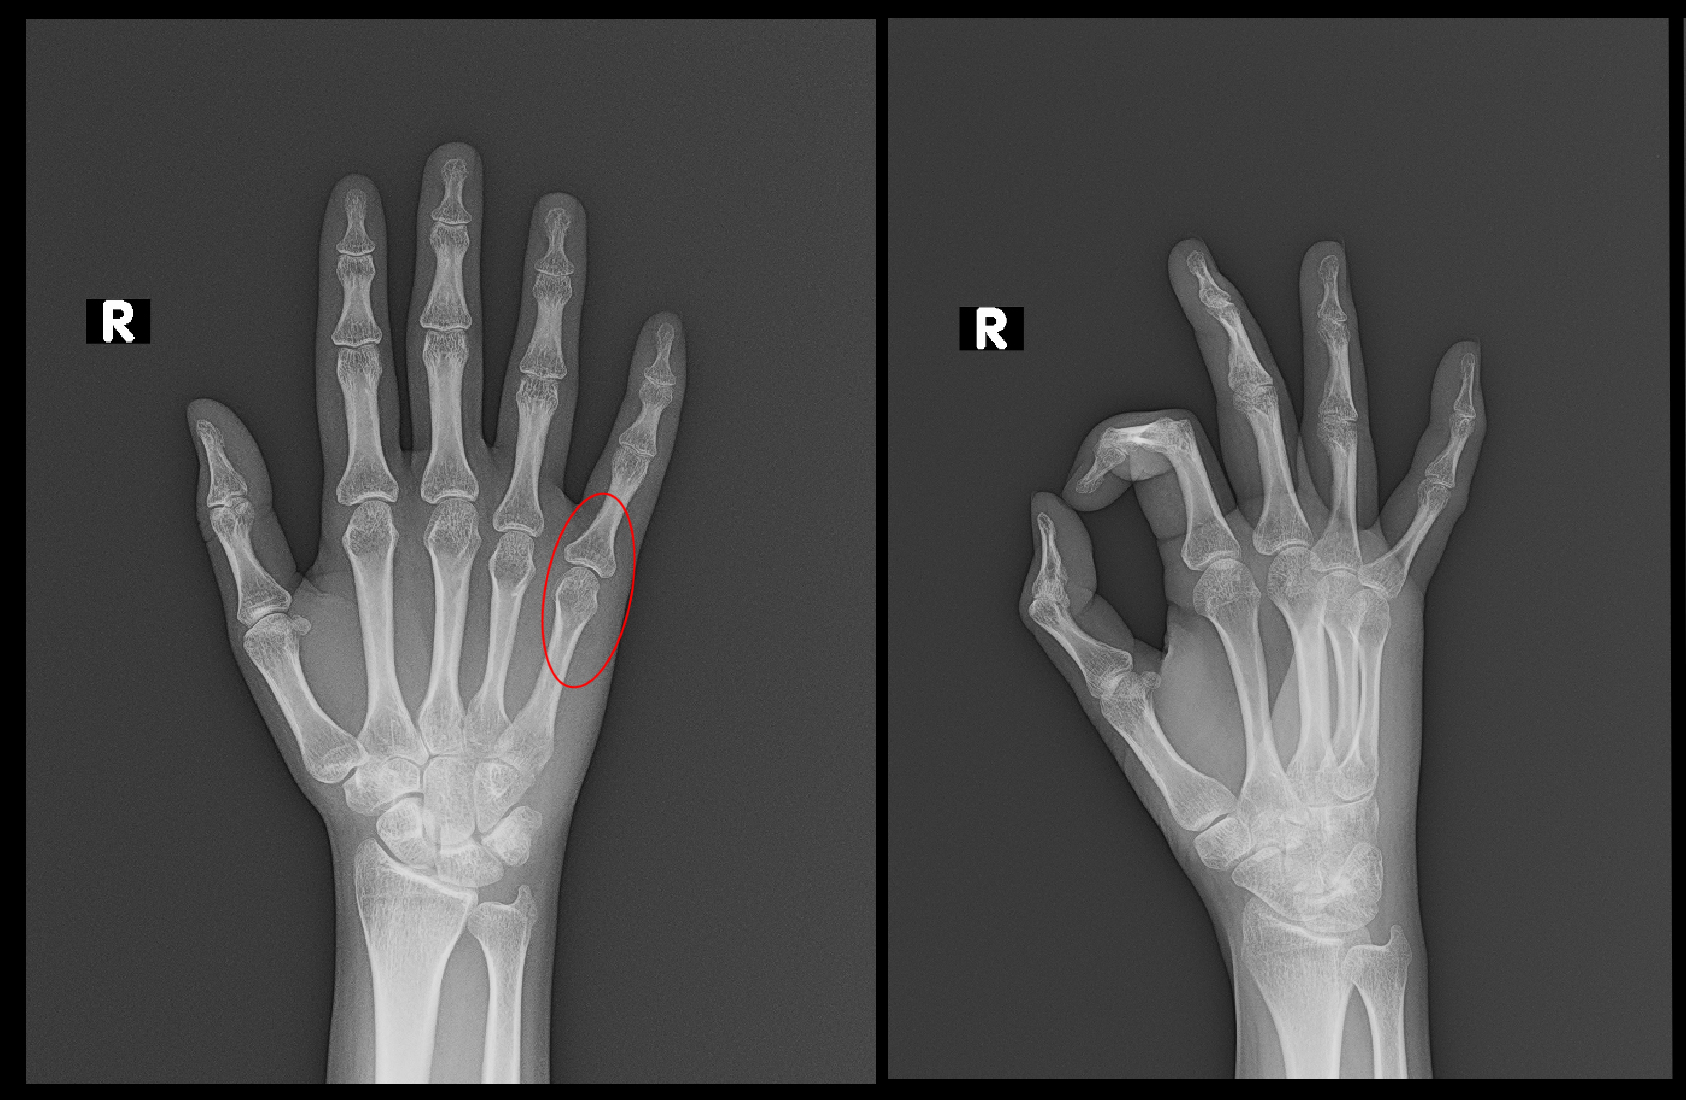

Y年4月12日自宅階段で1段落ちて、手すりに右小指を打撲して、14日に当院を受診されました。

当日のレントゲン像では異常はないため、打撲と診断し、薬と外用薬を処方しました。

ソフィー初診時Xp.jpg

しかし、私はレントゲンで把握できない骨折の症例があることを把握しているので、「良くならない場合には骨折の可能性もあるので、受診してください。」と伝えています。